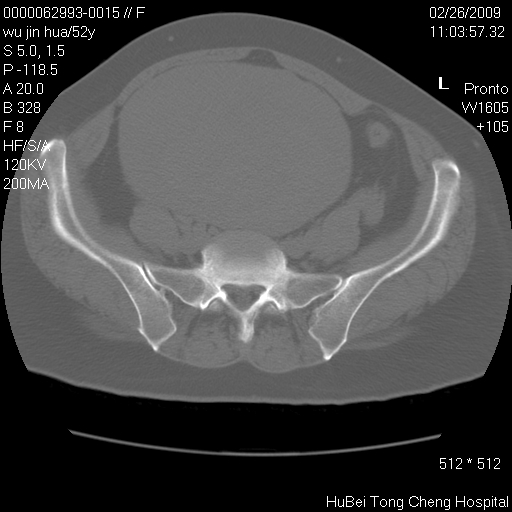

依据平片“腰椎退行性改变”报告,作椎间盘ct扫描时发现:

盆腔彩超报告:子宫肌瘤。(或许也漏诊了!)

囊腺瘤

影像表现:盆腹腔巨大占位,内密度均匀,边界清,未做强化。

来源:考虑来源于腹膜后肿瘤。

性质:以肉瘤可能性大。